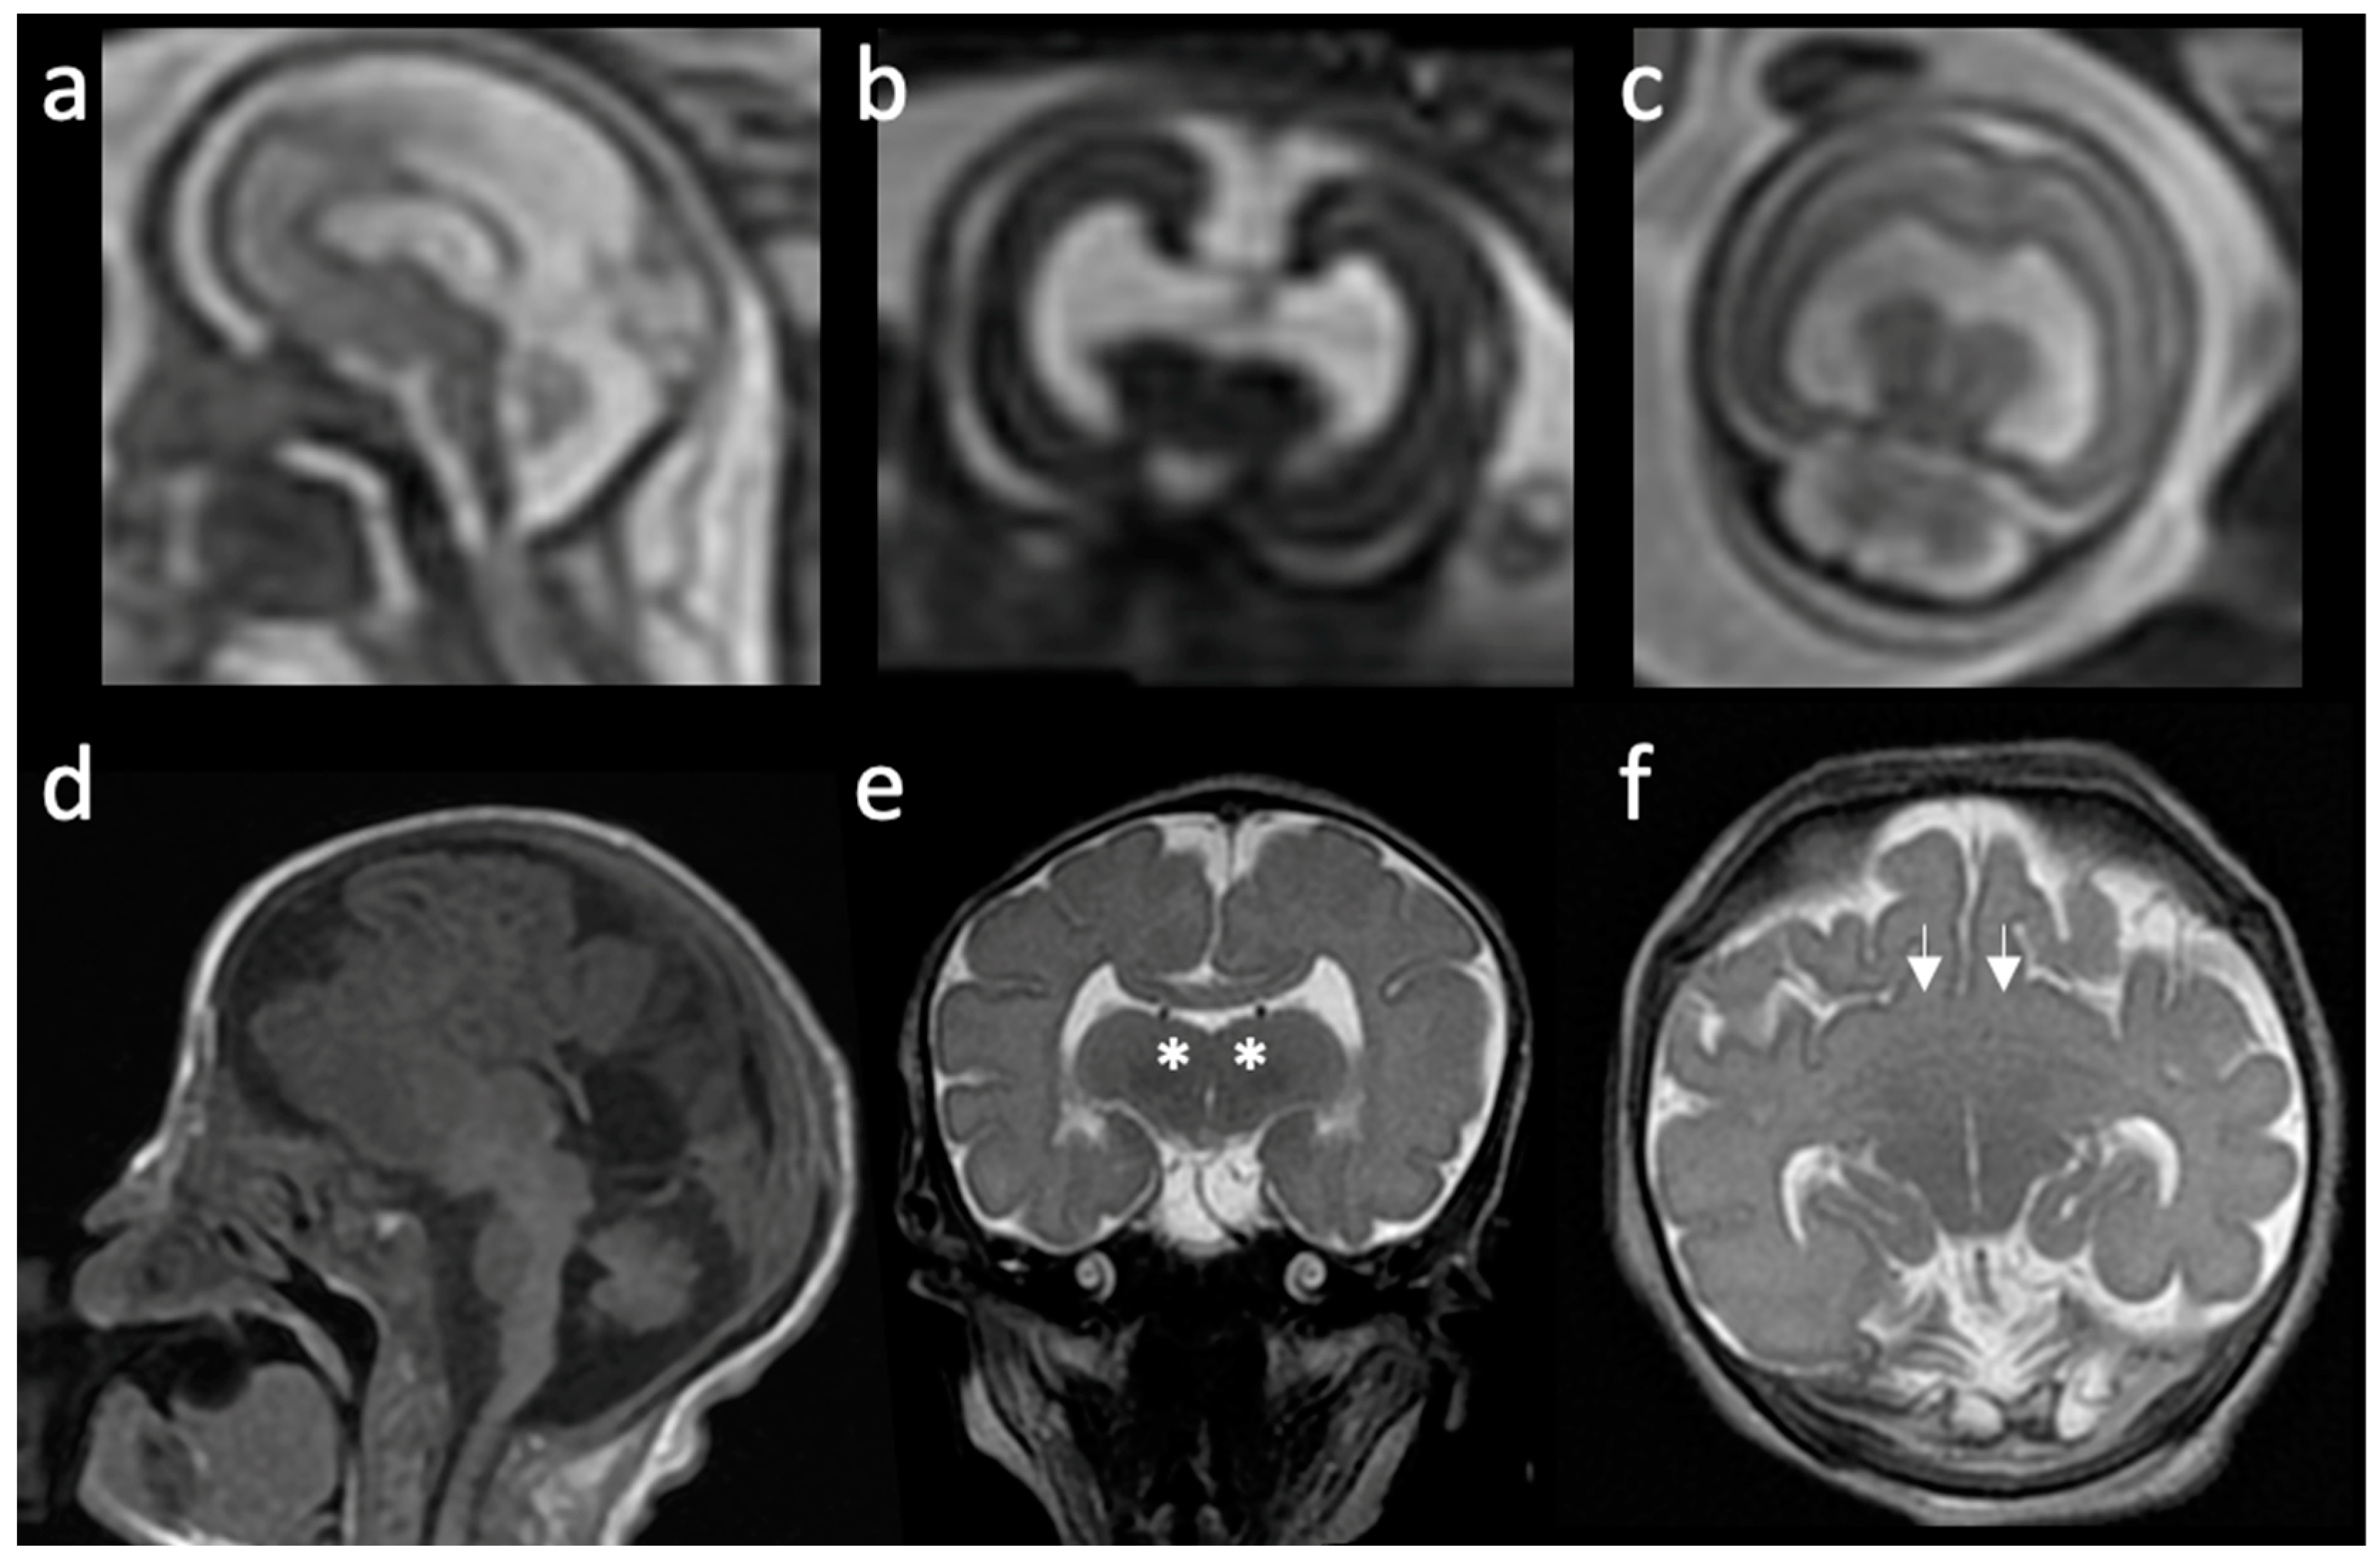

| Type | Main Features | References |

|---|---|---|

| Alobar | Absent separation of the cerebral hemispheres; Single “monoventricle”; Agenesis of the corpus callosum, absent third ventricle; Fusion of thalami and basal ganglia; Dorsal cyst is frequent; Significant midline facial defects. | [6,14,16,19,20] |

| Semilobar | Anterior lobes fail to separate; Interhemispheric fissure detected only posteriorly; Small, partially-formed third ventricle is often noted; Dorsal cyst may also be present; Midline craniofacial defects may be present or only subtle facial abnormalities. | [6,16] |

| Lobar | Only the most rostral-inferior parts of the frontal lobes are fused; Septum pellucidum is usually absent; Posterior half of the corpus callosum is formed; Varying degrees of basal ganglia and thalamic fusion; Midline craniofacial defects often absent or mild. | [6,16,21] |

| Middle interhemispheric variant (syntelencephaly) | Failure of separation of the posterior frontal and parietal lobes; Variable lack of cleavage of the basal ganglia and thalami; Absence of the body but presence of the genu and splenium of the corpus callosum. | [6,16,17,22] |

| Septopreoptic (minimal form) | Midline fusion restricted to the septal region or preoptic region of the telencephalon. | [16] |